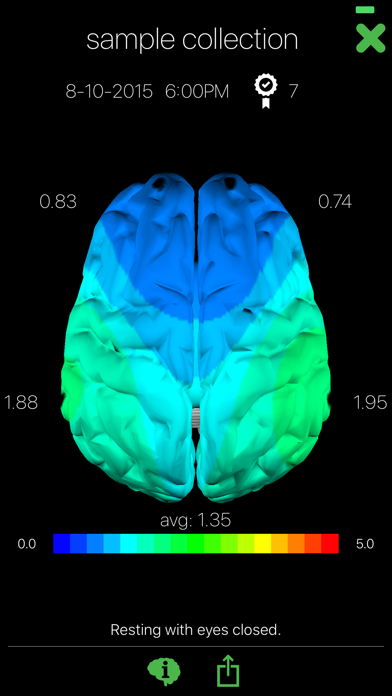

Have you ever wondered what your brain looks like? Opti Brain allows you to map your brain activity with the help of Muse, the brain sensing headband. Collect and save your brain data from your brain sensing hardware. Name and assign a quality to your collections to categorize and remember them. Then create and compare maps and movies of your brain activity. Opti brain also provide interpretations with each map you create.

The Opti Brain app is brought to you by Opti Brain, a company dedicated to helping you optimize your performance. Record your brain data during different activities (resting; critical thinking; before, during and after performance based sports and activities; etc.) and compare the patterns in your brain maps. Discover your BETTER THAN BEST™ brain pattern when you are performing at your full potential!

Have you ever wondered what your brain looks like? Opti Brain allows you to map your brain activity with the help of Muse, the brain sensing headband. Collect and save your brain data from your brain sensing hardware. Name and assign a quality to your collections to categorize and remember them. Then create and compare maps and movies of your brain activity. Opti brain also provide interpretations with each map you create.

The Opti Brain app is brought to you by Opti Brain, a company dedicated to helping you optimize your performance. Record your brain data during different activities (resting; critical thinking; before, during and after performance based sports and activities; etc.) and compare the patterns in your brain maps. Discover your BETTER THAN BEST™ brain pattern when you are performing at your full potential!